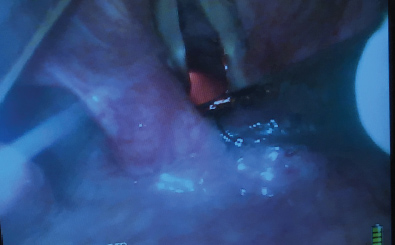

Figure 4: Video-laryngoscope (VL) view of a flexible intubation scope (FIS) passing over the arytenoids. The FIS is ante-flexed by pushing the thumb down.

Figure 5: Video-laryngoscope (VL) view of the flexible intubation scope (FIS) having passed the vocal cords. The FIS is retroflexed by pushing the thumb up.